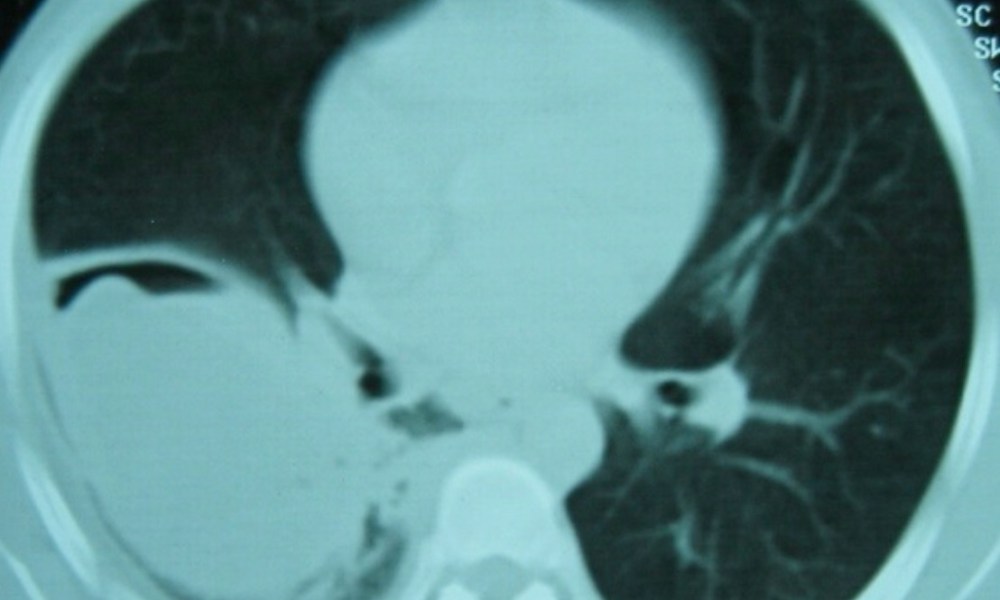

Not so much a clinical but a radiological vignette – a CT image from more than a decade ago.

Question: What is the radiological sign and what is the diagnosis?

The CT cut of the lungs shows a “water lily” sign (and thanks for those who suggested that it is an ugly or atypical “water lily”), which is almost diagnostic of a pulmonary hydatid cyst. This patient was seen more than a decade ago when I was in Peru for the famous Gorgas Diploma Course in Clinical Tropical Medicine. I cannot recommend this course highly enough, and there are now quite a number of distinguished alumni from Singapore.